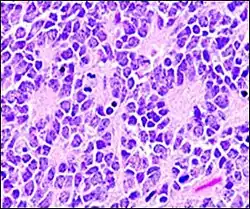

-

Micrograph of perivascular pseudorosettes -

A perivascular pseudorosette consists of a spoke-wheel arrangement of cells with tapered cellular processes radiates around a wall of a centrally placed vessel. The modifier “pseudo” differentiates this pattern from the Homer Wright and Flexner-Wintersteiner rosettes, perhaps because the central structure is not actually formed by the tumor itself, but instead represents a native, non-neoplastic element. Also, some early investigators argued about the definition of a central lumen, choosing “pseudo” to indicate that the hub was not a true lumen but contained structures. Nevertheless, this pattern remains extremely diagnostically useful and the modifier unnecessarily leads to confusion. Perivascular pseudorosettes are encountered in most ependymomas regardless of grade or variant. As such, they are significantly more sensitive for the diagnosis of ependymomas than true ependymal rosettes. Unfortunately, perivascular pseudorosettes are also less specific in that they are also encountered in medulloblastomas, PNETs, central neurocytomas, and less often in glioblastomas, and a rare pediatric tumor, monomorphous pilomyxoid astrocytomas.[2]